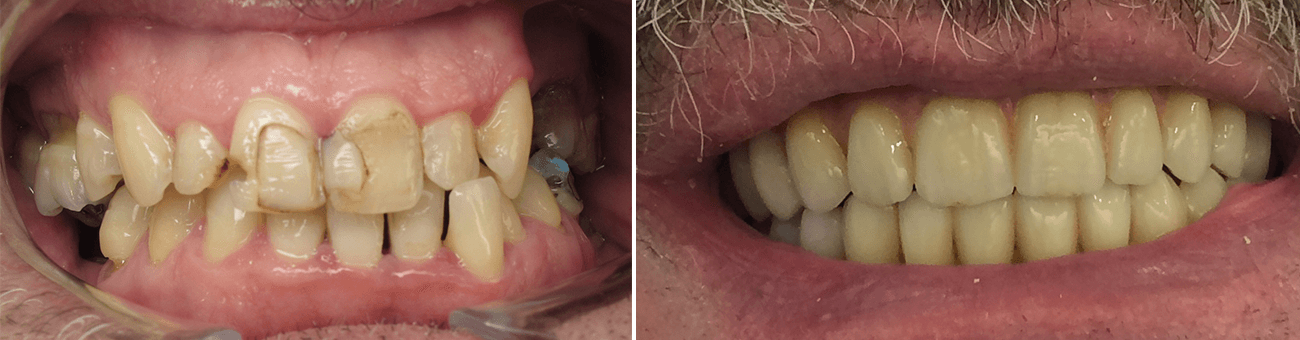

Paciente de 76 anos do sexo masculino

Motivo da consulta: Paciente desdentado total, procurava colocar dentes.

Plano de tratamento: Colocação de 4 implantes superiores e 2 implantes inferiores. Confeção de uma barra superior e colocação de 2 locators® na parte inferior. Confeção de uma prótese superior e outra inferior removível, com encaixes na barra e locators®.

A escolha deste plano de tratamento deve-se ao facto de o paciente querer uma solução total, mas não completamente fixa, uma vez que não tinha muita destreza manual para higienizar uma prótese fixa. Desta forma, conseguiu uma solução bastante retentiva (devido aos encaixes) mas que consegue remover para uma higienização correta.